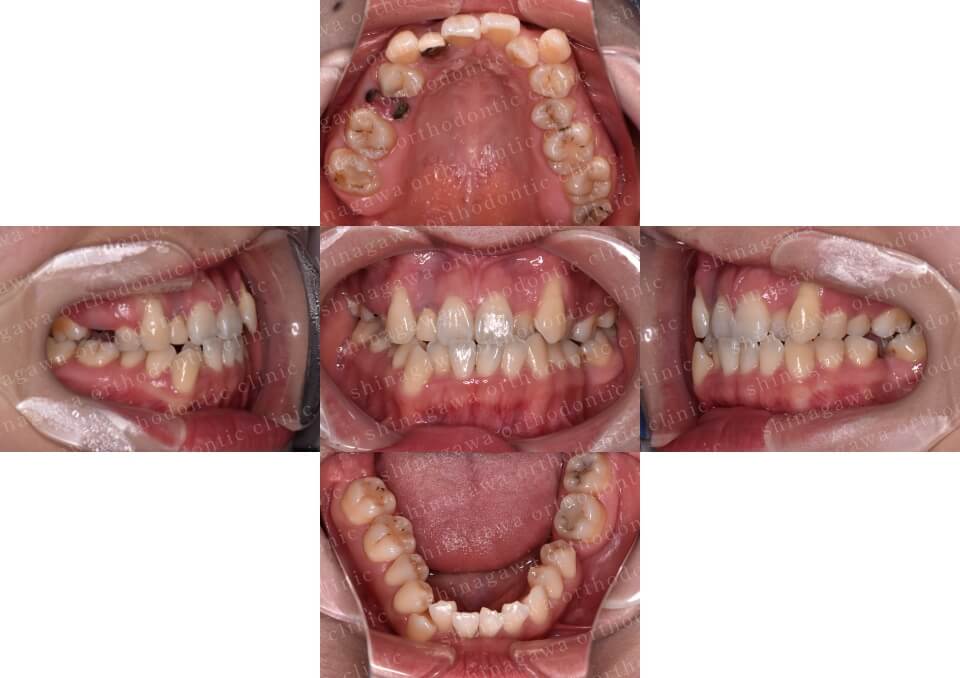

症例2

叢生、正中不一致

| 年齢 | 17 歳 |

|---|---|

| 性別 | 女性 |

| 住所 | 神奈川県横浜市 |

| 主訴 | ガタガタしている, 上下真ん中ずれ |

| 不正咬合の種類(診断) | 叢生, 正中不一致 |

| 装置 | (マウスピース型矯正装置)アライナー |

| 抜歯/非抜歯 | UR4, UL4, LR4, LL4 |

| 期間 | 18M |

| 費用 | 990,000 円 |

| リスク・副作用 | 矯正治療による歯の移動に伴う痛み, 虫歯, 歯肉退縮, 歯根吸収 |